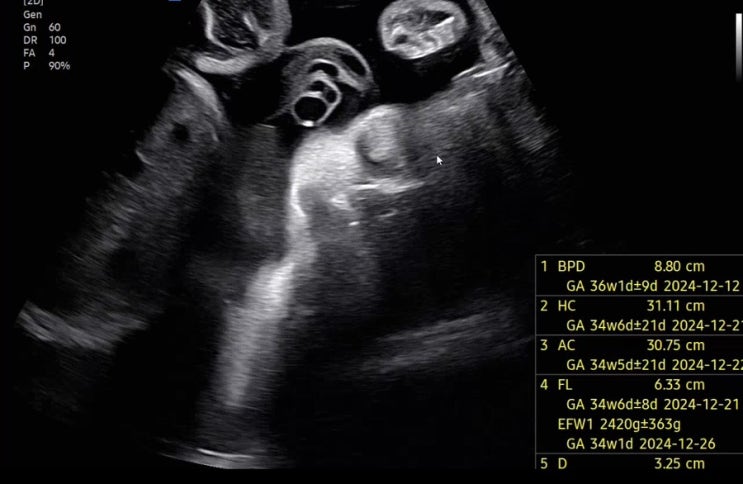

임신 36주차 / 드디어 혼인신고와 만삭사진까지! 인생에서 중요한 한 주였다!

36주차 증상 - 점점 더 강해지는 태동 태동이 강해 새벽에 잠이 잘 안온다ㅠ 12/4 3주만에 딱지 보러 가는 ...